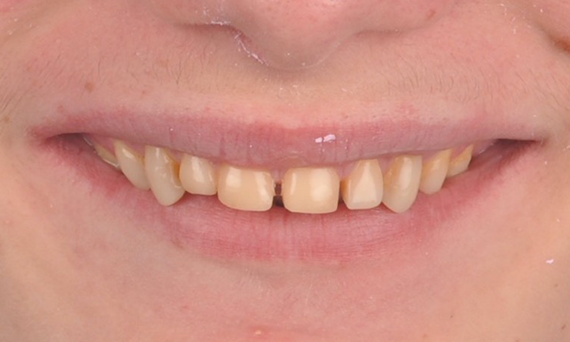

Before: Initial situation prior to orthodontic treatment.

After: Final result, 1 week post-operative.